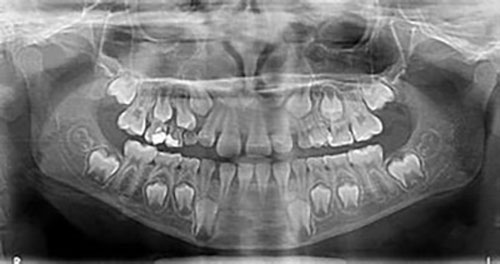

Radiografías infantiles

En los pacientes menores de 20 años, incluidos los adolescentes y los niños, los dientes se desarrollan más rápidamente. Por tanto, el tipo de radiografía dental debe adaptarse a la edad del paciente:

- Una radiografía panorámica entre los 6 y los 8 años para comprobar que los dientes están completos;

- Una radiografía panorámica entre los 10 y los 13 años para asegurarse de que los dientes no están apiñados;

- Una radiografía panorámica entre los 18 y los 20 años para controlar el crecimiento de las muelas del juicio.

Salvo en casos excepcionales, las radiografías dentales no son necesarias en niños menores de 5 años.

Lo ideal es vigilar la salud bucodental de tu hijo a partir de los 5 años para detectar precozmente cualquier problema y evitar complicaciones.